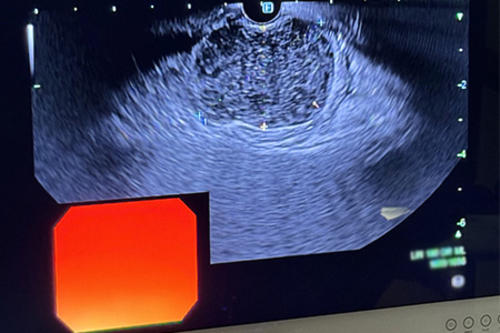

El médico guatemalteco Antonio Mendoza Ladd, director médico de endoscopia de UC Davis Health en Estados Unidos, lideró la primera biopsia endoscópica guiada por ultrasonido con una nueva aguja. El método podrá ayudar a detectar cáncer y podría ofrecer a los pacientes un mejor tratamiento y resultados.

Mendoza Ladd realizó los procedimientos utilizando un instrumento llamado EndoDrill G, que se usó para hacer una biopsia de tumor estomacal gastrointestinal y dos tumores pancréaticos. Los procedimientos fueron realizados en Estados Unidos con el innovador instrumento.

La tecnología permite que las muestras de tejido recolectadas en la biopsia sean obtenidas con una perforación eléctrica a alta velocidad, lo que permite que las muestras de tejido sean tomadas con alta precisión. Además, se permite una ubicación profunda.